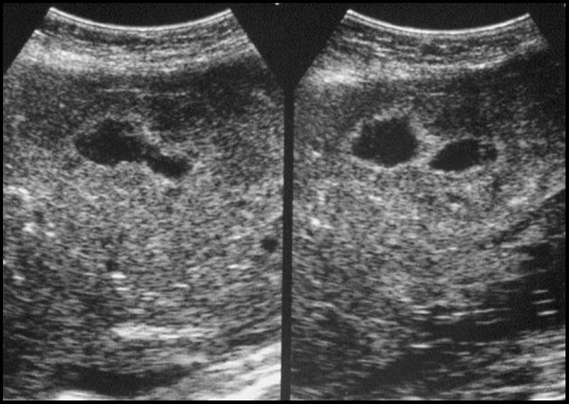

Cancer de l’endomètre. Contours irréguliers. Pas de limites nettes avec le myomètre

Myomètre aminci voire infime